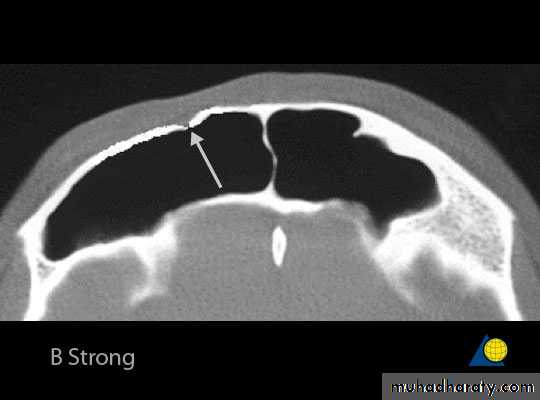

Frontal Sinus